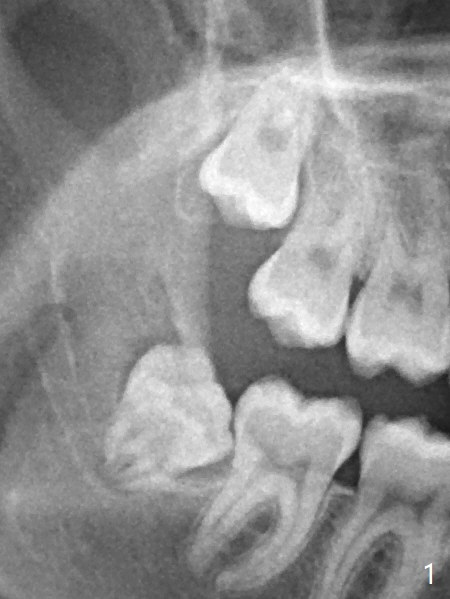

Xin Wei, DDS, PhD, MS 1st edition 11/21/2020, last revision 11/23/2020